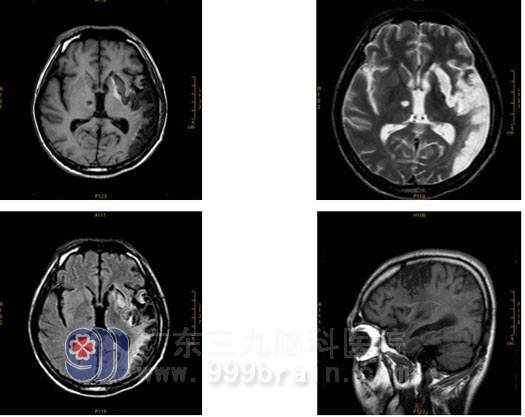

一个半月后复查:

▲ 原梗塞区病变脑软化灶形成,周围胶质增生,相应区域局限性脑萎缩。MRA检查示左侧大脑中动脉仍闭塞。